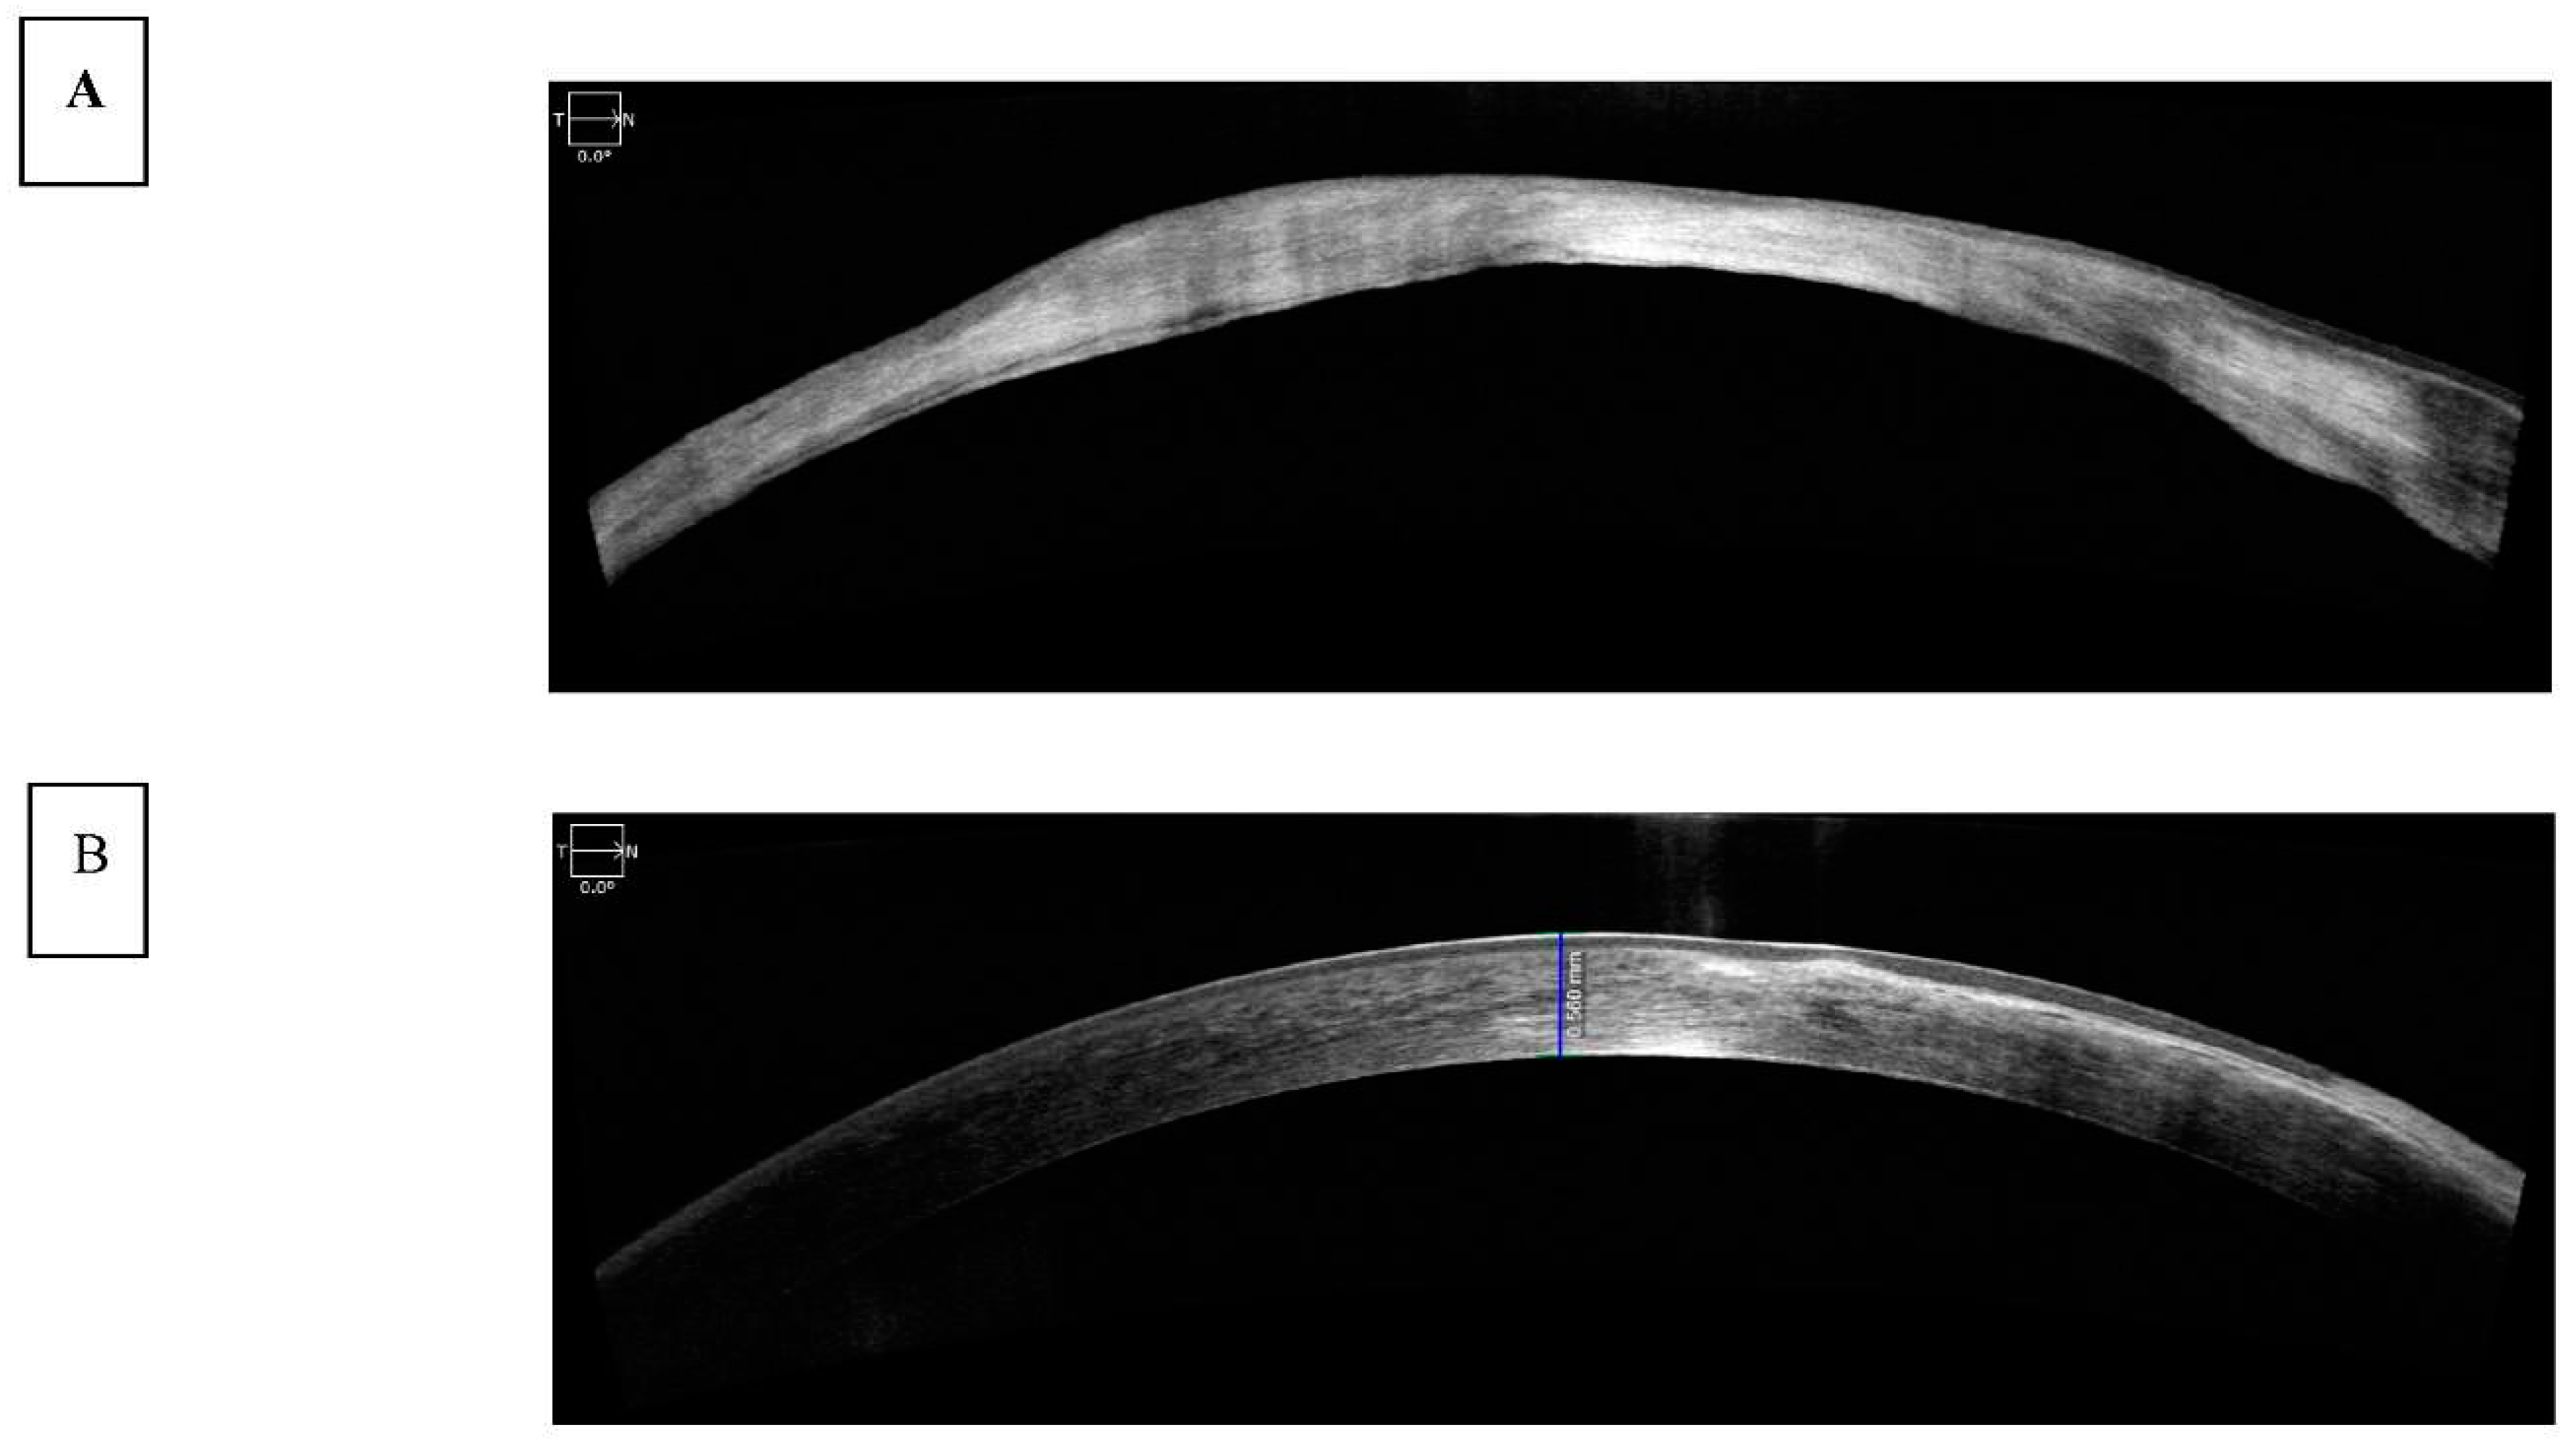

Spectral-domain (SD) OCT evaluates the frequency spectrum of the interference between a stationary reference mirror and the reflected light, allowing spatial and structural information to be measured simultaneously at all echo time delays (axial pixels). The benefit of simultaneous assessment of all axial-depth scan (A-scan) pixels is the significant increase in scanning speed up to 100,000 A-scans/s with commercial devices and up to 20.8 million A-scans/s with research devices [19]. In addition, a higher resolution, up to 2 microns, was achieved via a broader spectrum light source [7,22]. SD-OCT has been used to assess corneal pathology such as scarring and thinning (Figure 3A) and measure corneal thickness and show epithelial layer thickness (Figure 3B).

Figure 3. A and 3B: SD-OCT images of the cornea showing A) Corneal scarring and thinning in a patient following acanthamoeba keratitis and B) corneal thickness measurement and epithelial layer imaging.